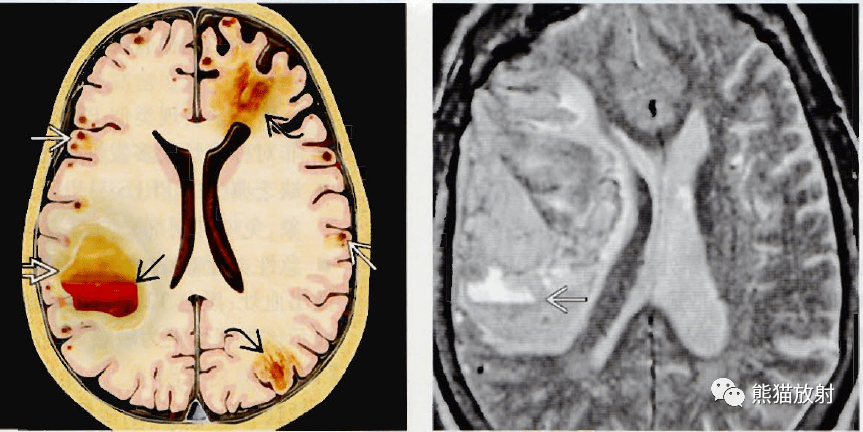

病例分享脑淀粉样血管病病例分享及概述